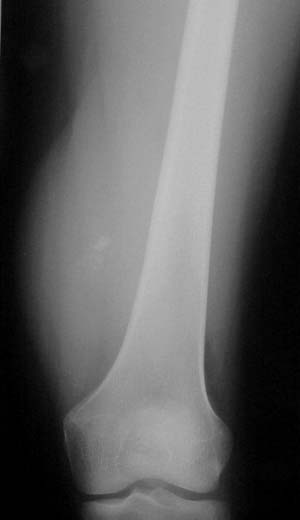

avenjers71 (7) گزارش تخلف سرطان استخوان اسکلت انسان را استخوان , که جسم جامدی است تشکیل می دهد و به شکلهای گوناگون در بخشهای مختلف بدن قرار دارد . بخش بیرونی استخوان بسیار سفت و سخت و مرکب از املاح معدنی و مواد آلی است .سرطان استخوان از سنین شیرخوارگی تا سالمندی می تواند ایجاد شود و سبب فلج عضو و یا مرگ فرد مبتلا شود . سرطان استخوان به سارکوم Sarcome نیز شهرت دارد و در ت... 9 0 0 59 5 سال پیش